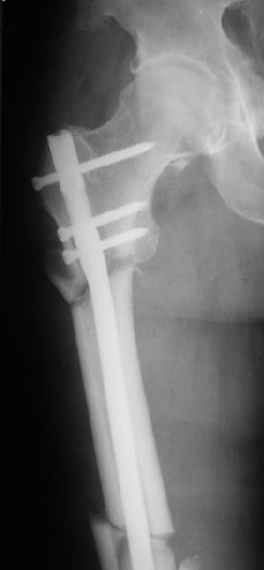

В частности, на проксимальном конце сделано еще одно дополнительное статическое отверстие. Можно ввести в проксимальном отделе 4 винта, из них 3 статические (2 в круглые отверстия и 1 по нижнему краю овального). Картинки в приложении. На дистальном конце стержня тоже кое-что улучшено. Спрашивайте в аптеках, как говорится. Выпускается предприятием "ЦИТО" (Москва), то есть это малобюджетное решение.

Конечно, мы не синтезируем остеопорозые вертельные переломы согласно прилагаемому примеру, винты 6 мм вырежутся. Но у более молодых при хорошем качестве кости такие или подобные гвозди с поперечным расположением винтов вполне применимы для меж- и подвертельных переломов.

Это было года 2,5 назад, мы тогда еще уточняли возможности шинирования с угловой стабильностью гвоздем с поперечным расположением винтов при переломах проксимального отдела бедра. Пациенту не пришлось приобретать намного более дорогой рекон или проксимальный гвоздь. В приложении еще несколько примеров применения того гвоздя при высоких переломах бедра, в том числе с более латеральной точкой входа. Гвоздь изгибаем для этого.